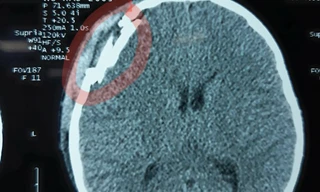

TPO - Lúc 23h ngày 22/3, tại Bệnh viện Chợ Rẫy (Thành phố Hồ Chí Minh), ông Huỳnh Văn Nén, “người tù thế kỷ” đang được chụp cắt lớp (CT) để xác định tình trạng chấn thương sọ não. Bà Nguyễn Thị Cẩm, vợ ông Nén cho biết.